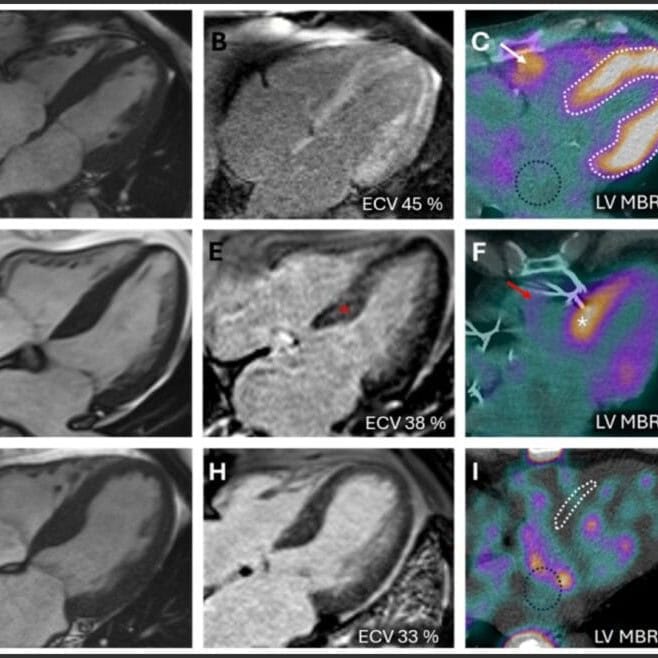

JNC-May2025-EditorsChoiceFig-768x658